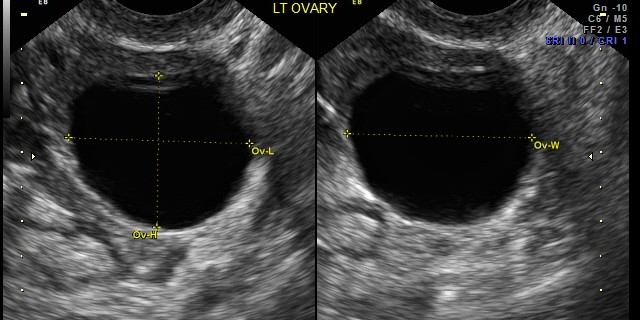

The Royal College of Obstetricians and Gynaecologists have issued updated guidance on diagnosis and management of ovarian cysts